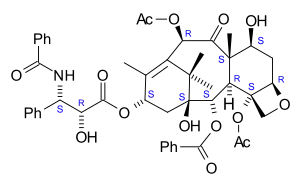

The nomenclature for paclitaxel is structured on a tetracyclic 17-atom skeleton. There are a total of 11 stereocenters. The active stereoisomer is (−)-paclitaxel (shown here).

As of 2006, five additional research groups had reported successful total syntheses of paclitaxel: Wender et al. in 1997, and Kuwajima et al. and Mukaiyama et al. in 1998 with further linear syntheses, and Danishefsky et al. in 1996 and Takahashi et al. in 2006 with further convergent syntheses. As of that date, all strategies had aimed to prepare a 10-deacetylbaccatin-type core containing the ABCD ring system, followed generally by last stage addition of the "tail" to the 13-hydroxyl group.[45]